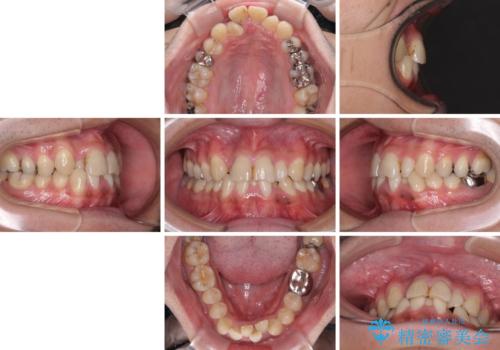

重なって磨きにくい上下の前歯 ワイヤー装置での抜歯矯正

- 前歯のデコボコを改善したいと来院された患者様です。

口元の突出感はないものの、上顎前歯のデコボコが著しかったため、上下顎左右小臼歯4本を抜歯することとしました。

上下の正中位置を改善するため、右下は第一小臼歯を、その他は第二小臼歯を抜歯することとしました。

第二小臼歯抜歯の矯正治療は、治療期間が長引くことが多いですが、動きが非常に良く、予定の治療期間で終えることができました。

上下の正中も思っていた以上に良い位置に改善されました。